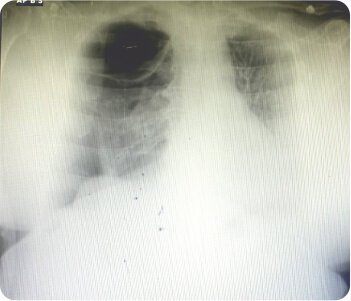

B/l Bullous Lung Disease with Spontaneous Right Sided Pneumothorax

On initial evaluation, X-ray was found to be radiolucent in right upper and lower zone suggestive of right sided pneumothorax. 2D Echo revealed concentric LVH / no rwma. CT chest (plain) revealed gross right pneumothorax with mild tracheal shift to left possibly due to rupture of emphysematous bullae. Subpleural emphysematous changes were noted in left lung with large bullae on both sides. Patient was taken up for emergency thoracostomy under aseptic conditions with the chest tube placed in the right 4th intercoastal space. Post procedural CXR was taken, ICD was in place. During the hospital stay, patient was closely monitored for desaturation and patient was put on oxygen support, antibiotics, nebulization, thyroid medication. Repeat CT chest revealed ICD in place with right gross pneumothorax with sub pleural bullae/ cysts projecting into pneumothorax and multiple cysts of varying sizes and para septal emphysematous bullae in left lung. Alfa 1 antitrypsin levels were normal. Patient was diagnosed as a case of B/L bullous lung disease with spontaneous right sided pneumothorax.

Chest radiograph showing right apical bullae